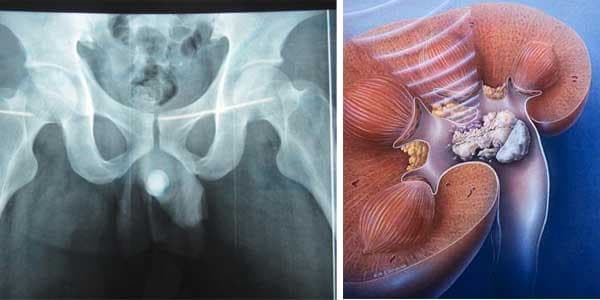

Tìm hiểu về bệnh sỏi niệu đạo

Niệu đạo là một ống dài nối từ bàng quang ra lỗ sáo (lỗ tiểu) để đưa nước tiểu ra ngoài. Niệu đạo rất dễ mắc nhiều bệnh lý khác nhau như viêm niệu đạo hoặc sỏi niệu đạo. Mời độc giả cùng tìm hiểu về bệnh sỏi niệu đạo qua bài viết dưới đây.

Sỏi niệu đạo thường gặp ở nam giới nhiều hơn nữ giới. Sỏi niệu đạo có thành phần hóa học như sỏi thận, sỏi ở bàng quang, chủ yếu là oxalate, urat, phosphate. Bệnh được hình thành do nhiều nguyên nhân khác nhau gây ra như: